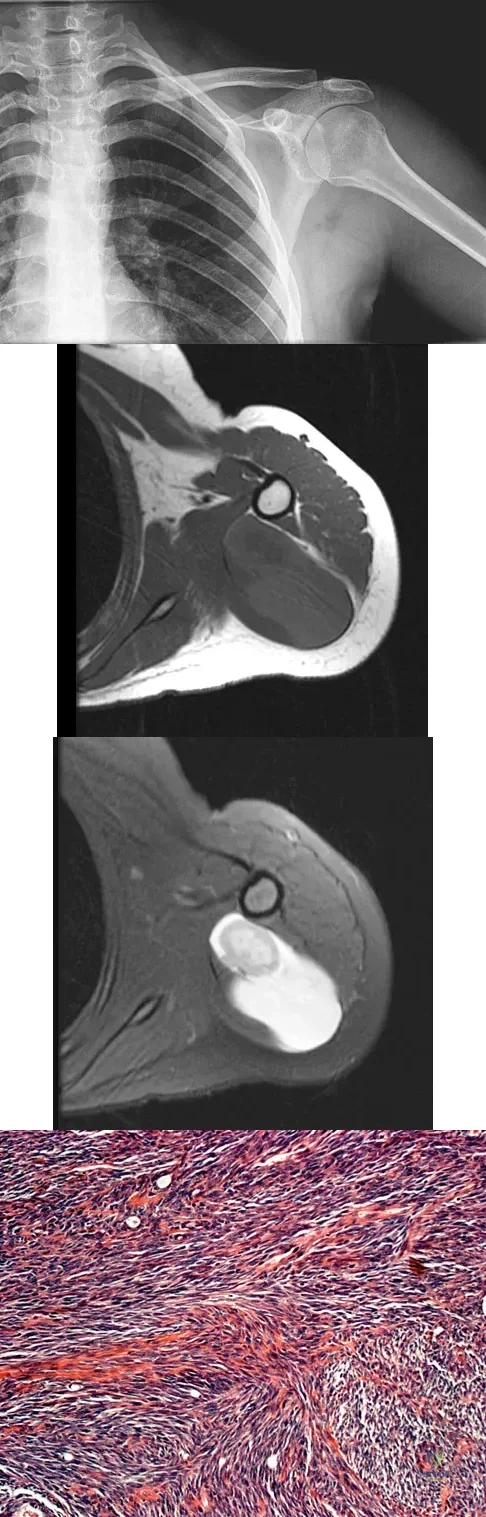

Question 26

A 47-year-old woman has had left medial clavicle pain for the past 6 months. History is remarkable for mediastinal non-Hodgkin's lymphoma, treated with mantel radiation 22 years ago. A radiograph, CT scan, MRI scan, and a biopsy specimen are shown in Figures 68a through 68d. What is the most likely diagnosis?

Explanation